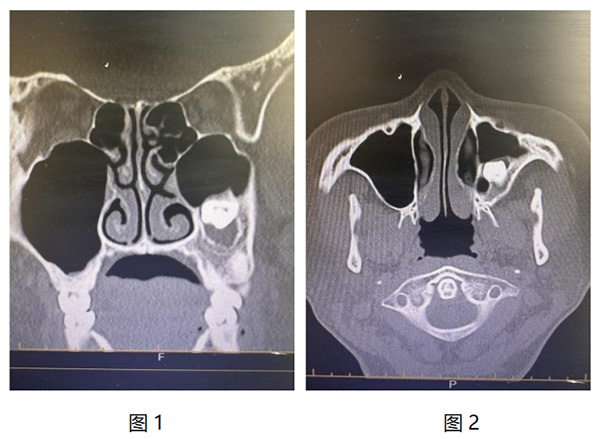

近日(ri),我(wo)院耳鼻咽喉頭頸外科(ke)成(cheng)功爲(wei)一(yi)名(míng)特殊病症患者實施了(le)高(gao)難度手術(shù)。患者因“牙片檢(jian)查時髮(fa)現(xian)上颌窦阻生(sheng)齒伴囊腫形成(cheng)1月”入院,經(jing)鼻窦CT檢(jian)查,可(kě)見其左側上颌窦內(nei)存在(zai)高(gao)密度影,且周圍有(yǒu)軟組織包繞,診斷(duan)爲(wei)上颌窦阻生(sheng)齒伴囊腫形成(cheng)。(圖1、2)。